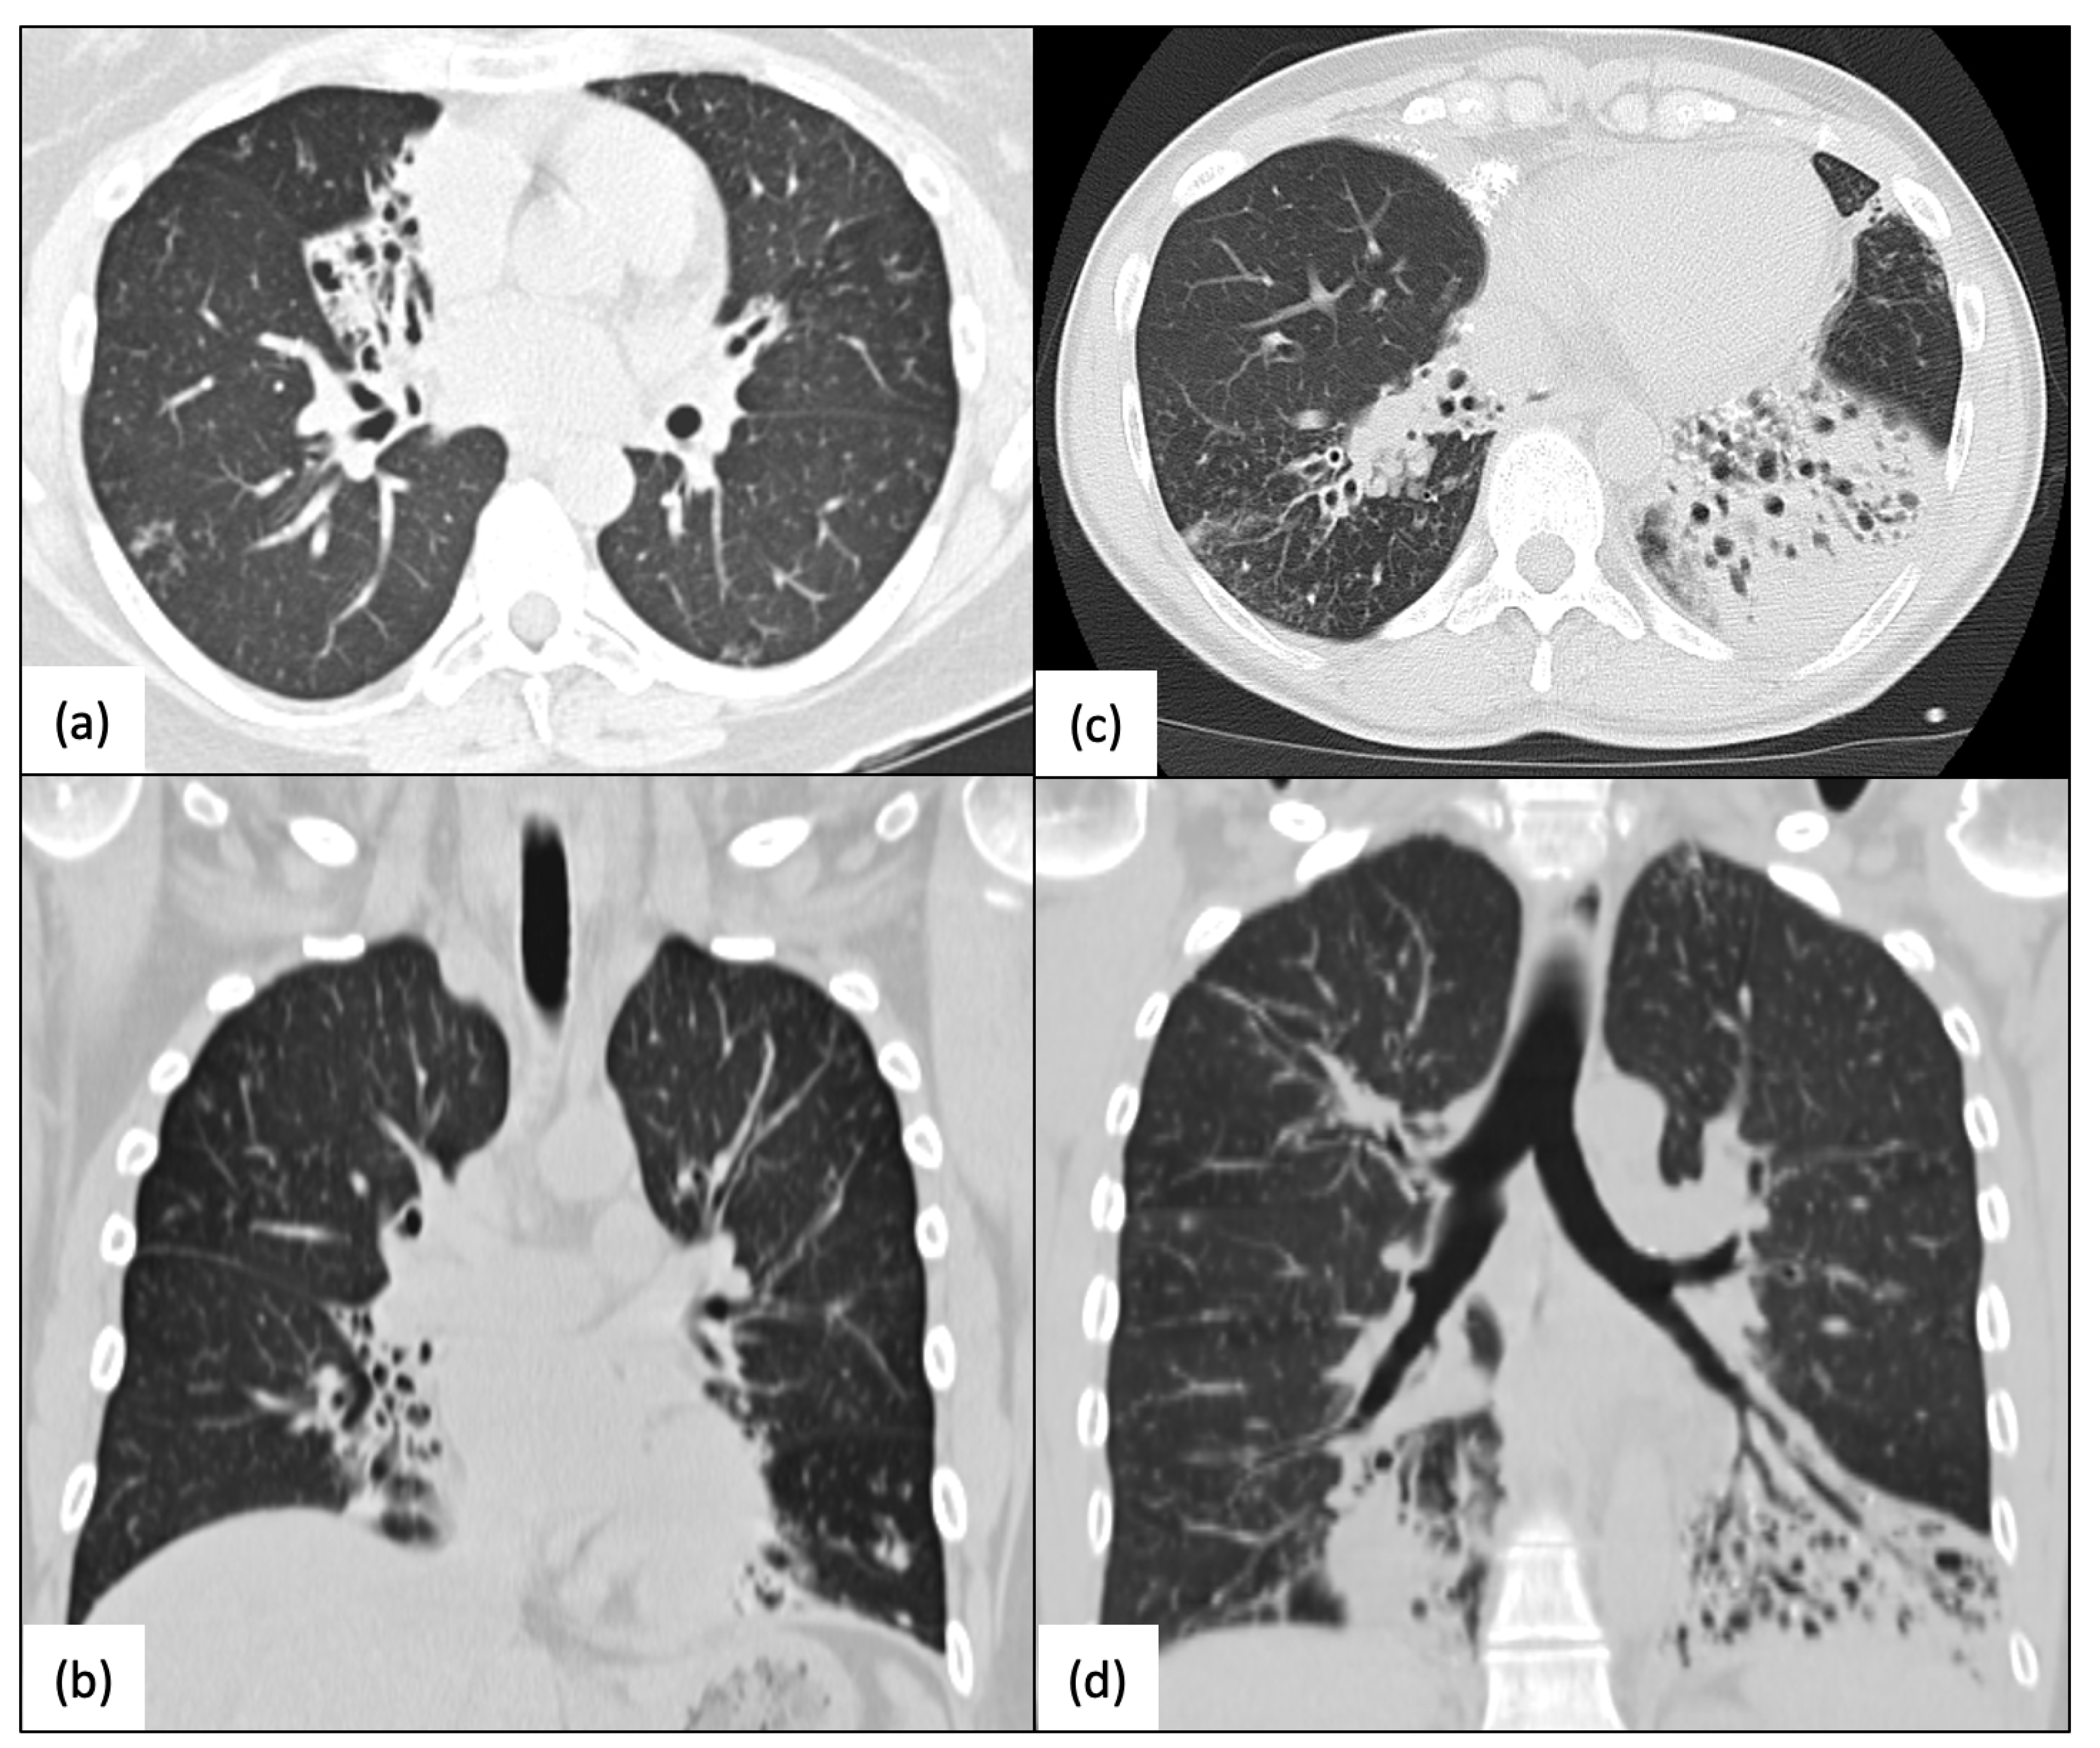

4.1. Pulmonary Disease in Humans with the RSPH4A Mutation